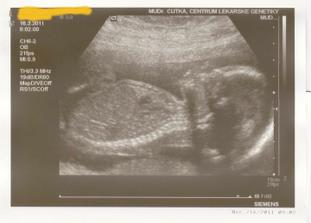

8.2.2011 čtvrtá kontrola (16tt) - výsledky z prvního doběru krve dobrý, nabrán odběr na triple test, dle ultrazvuku mimi v pořádku, dána pozvánka na 3D ultrazvuk na genetiku, půjdeme i s tatkou 🙂

16.3.2011 - 3D ultrazvuk - genetické centrum - vše je OK